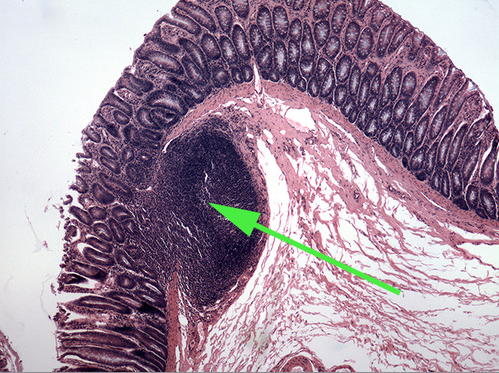

The diffuse lymphatic tissue found in the structure marked by the green arrow is called peyer's PATCH

The green arrow is indicating the peyer's patch in this area of the small intestine. It is made up of a dense accumulation of what kind of cells?//lymphocytes

The green arrow is indicating a tonsilar crypt

diffuse lymphatic tissue called peyer's patches in the wall of the intestinal tract.